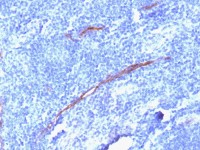

IHC-P analysis of human rectal cancer tissue using GTX03355 TJP2 antibody.

Antigen retireval : Heat mediated antigen retrieval was performed in EDTA buffer (pH8.0, epitope retrieval solution)

Dilution : 2μg/ml